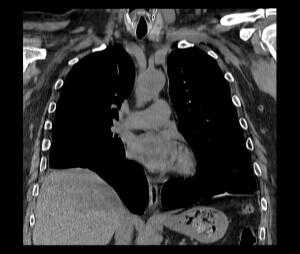

На КТ снимках синей стрелкой указан долевой ателектаз, а красной стрелкой опухоль, которая обтурирует левый верхний долевой бронх (центральный рак легкого.

КТ органов грудной клетки. Ателектаз верхней доли правого легкого, обусловленный злокачественной опухолью правого верхнедолевого бронха